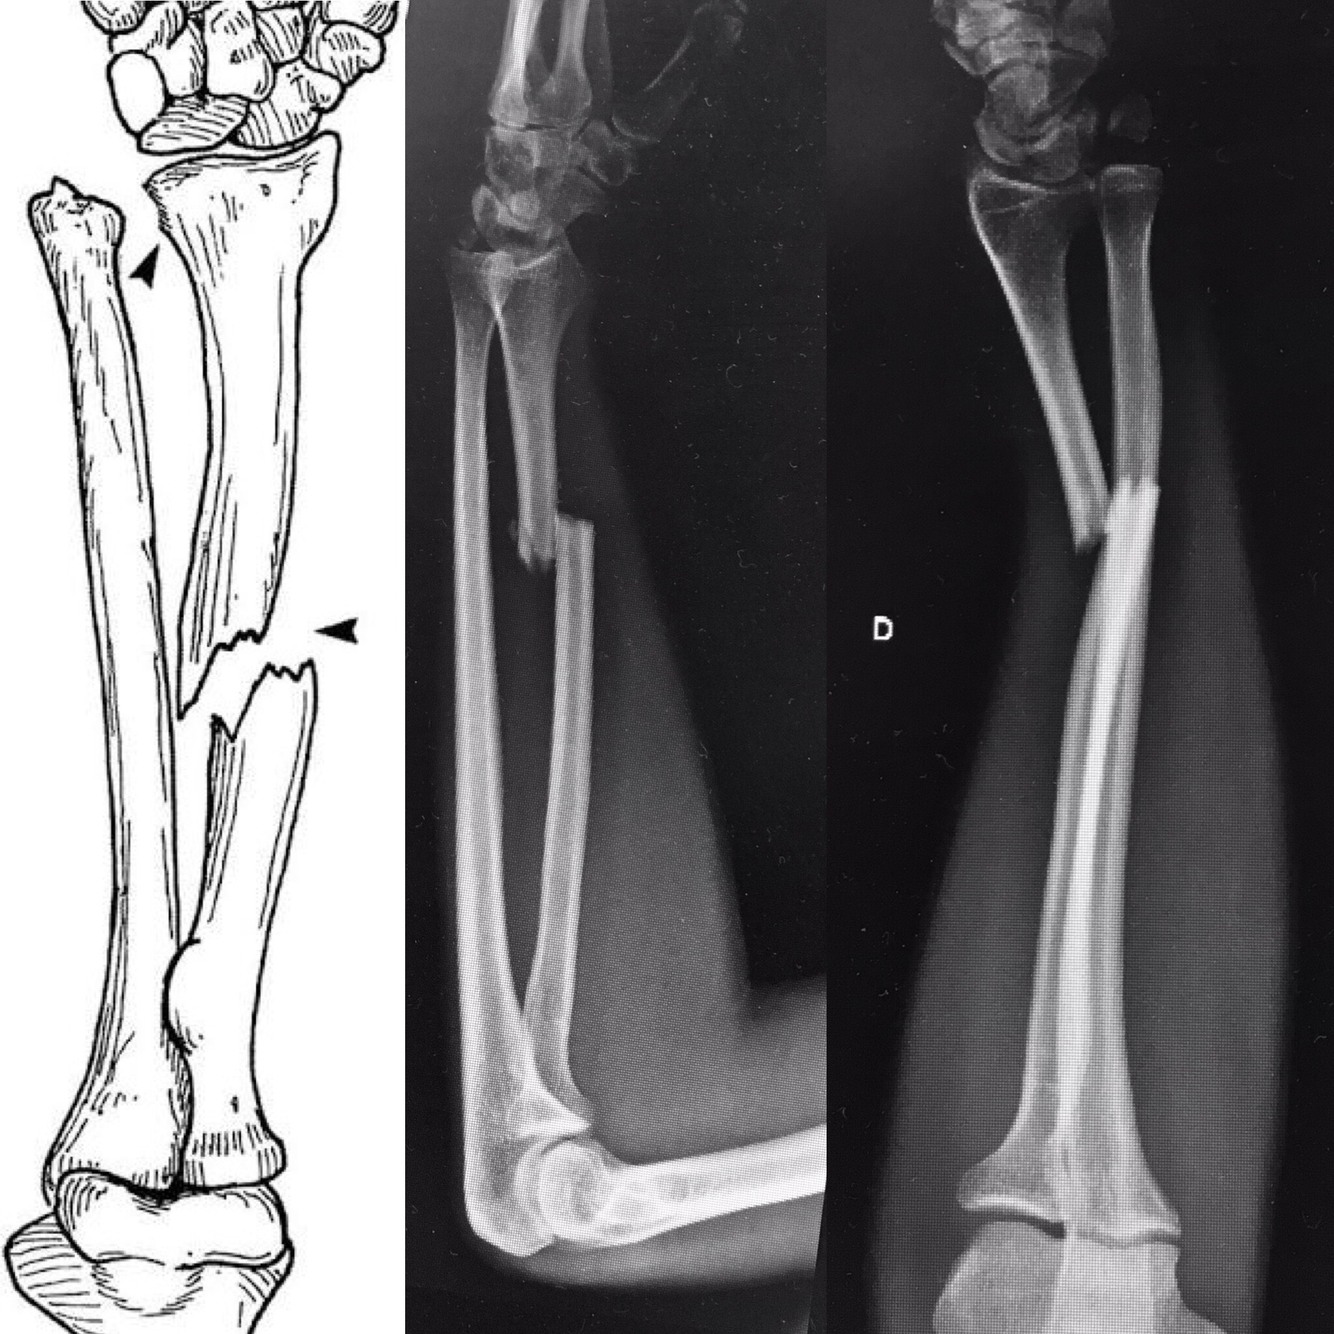

Fratura-luxação de Monteggia

Fratura diafisária proximal da ulna, associada à luxação da cabeça do rádio.